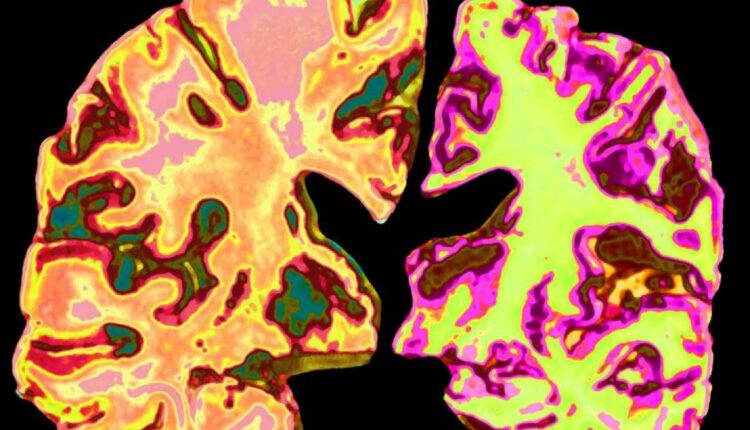

07 Ağustos 2025, 21:57 (TSİ) – Harvard Tıp Fakültesi ve Rush Üniversitesi’nden bilim insanlarının Nature dergisinde yayımlanan yeni bir araştırması, Alzheimer hastalığının gizemini çözmede büyük bir adım attı. Araştırmacılar, beyindeki lityum eksikliğinin Alzheimer’ın başlangıcında kritik bir rol oynadığını ve bu eksikliğin hafıza kaybı, amiloid plaklar ve tau yumakları gibi hastalığa özgü sorunları tetiklediğini ortaya koydu. Ancak daha da heyecan verici olanı, lityum orotat adı verilen bir lityum takviyesinin bu etkileri tersine çevirebileceği ve beyni adeta “gençleştirebileceği” bulgusu!

İnsan beyin dokularında yapılan analizler, Alzheimer hastalarının beyinlerinde lityum seviyelerinin belirgin şekilde düşük olduğunu gösterdi. Hafif bilişsel bozukluğu olan kişilerde ise lityumun amiloid plaklara “hapis” olduğu ve beyin tarafından kullanılamaz hale geldiği tespit edildi. Bu, lityum eksikliği ile plak birikimi arasında tehlikeli bir döngü yarattığını düşündürüyor.